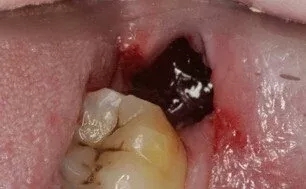

干槽症又称局限性牙槽骨炎,拔牙后发病率大致在15%左右,下颌阻生智齿拔除后,发病概率相对较高。

19世纪末,国外一名患者下颌阻生智齿拨除后,疼痛严重并向耳颞部放散,检查时发现拨牙窝干燥、空虚、无渗出物。“干槽症”的名号从此传开。

剧烈疼痛,是人们对干槽症的第一印象。这种疼痛一般会保持3-5天,甚至牵连拔牙同一侧的耳朵,太阳穴。更糟的是,止疼药对这种疼痛效果不佳。

干槽症带来的疼痛,往往不会立即发生,可能在拔牙后两三天才出现。这种疼痛带有向耳颞部、下颌等部位的放射。如果牙槽窝存在腐败组织,会出现恶臭。